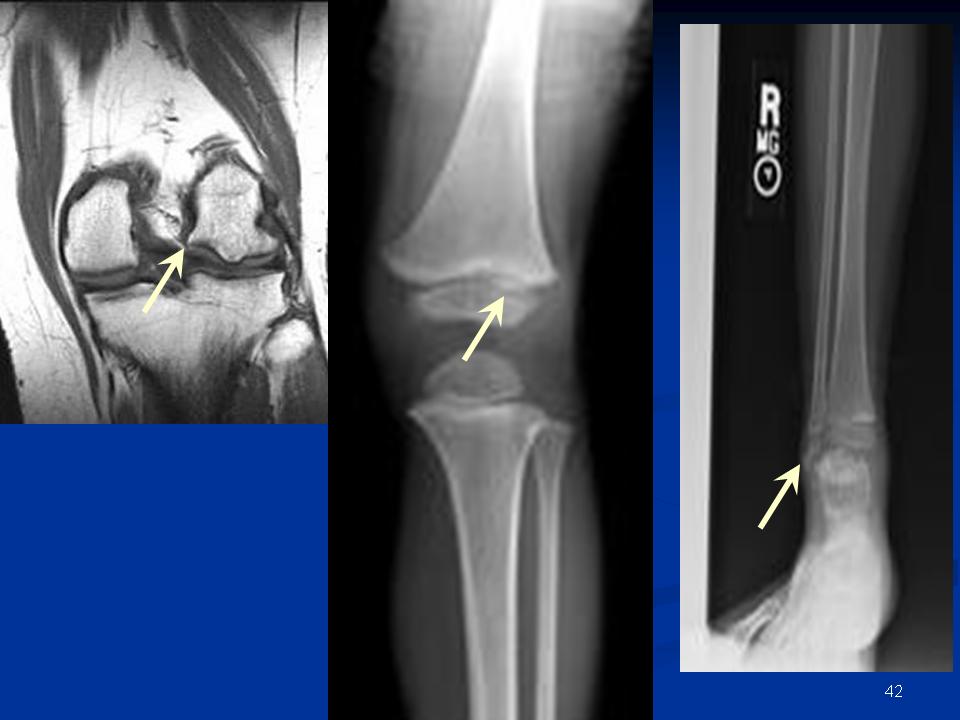

Рентгеновские снимки доброкачественных опухолей костей